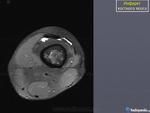

Женщина 1952 г.р.,направлена с диагнозом остеоартроз

Энхондрома, инфаркт кости, хондросаркома. Я в заключении такой бы диф. ряд написал.

На мой взгляд имеет место быть "Хрящевая матрица"

+1.Энхондорма? Хондросаркома?? Для уточнения рекомендована КТ коленного сустава.

Значит, что имеются элементы хрящевой ткани. Есть вероятность наличия хрящевой опухоли.

Большое спасибо за комментарии!Сегодня пациентка принесла архивные снимки обоих коленных суставов,за 2008,2009,2011 года -картина такая же и на тех снимках,а на снимках правого коленного сустава за 2008 год такой же участок(немного меньших размеров) в области метадиафиза большеберцовой кости.Ни МРТ ни КТ никогда не делала.

Энхондрома все же не исключается.

Инфаркт костного мозга.